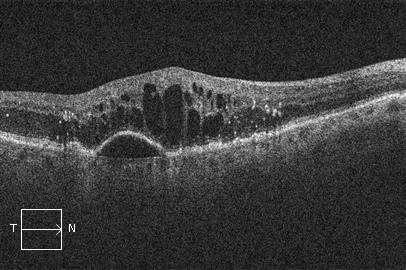

La Degeneración Macular Asociada a la Edad (DMAE) húmeda o exudativa se trata con inyecciones intravítreas de fármacos antiangiogénicos. Suelen ser necesarias varias inyecciones antes de lograr controlar el crecimiento de los vasos sanguíneos responsables de la enfermedad. Las inyecciones intravítreas pueden realizarse en una sala limpia o quirófano, con anestesia local y en condiciones de esterilidad.

OCT. DMAE húmeda o exudativa después del tratamiento con inyecciones intravítreas.